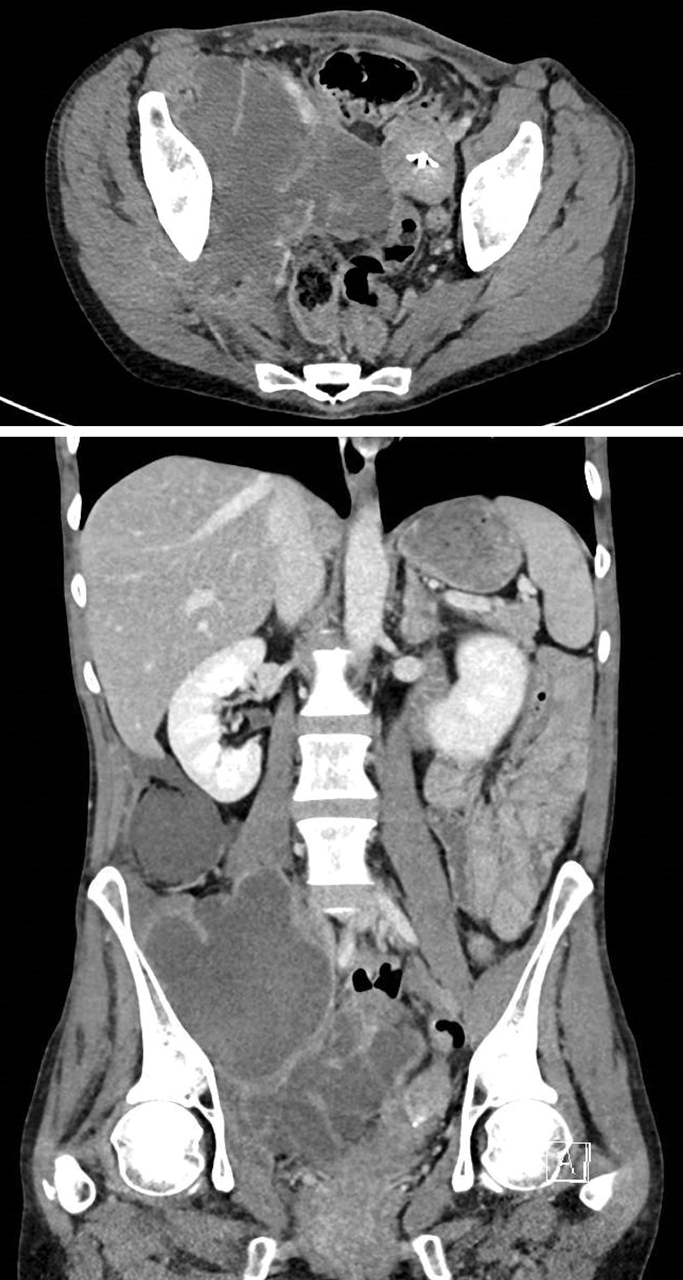

Une femme de 50 ans consulte pour des douleurs abdominopelviennes latéralisées à droite, évoluant depuis 15 jours.

Elle est fébrile (38,2 °C). Les leucocytes sont à 21 000/mm3 et la protéine C réactive à 400 mg/L. Un scanner est réalisé.

La patiente est porteuse d’un stérilet non changé depuis de nombreuses années.

Quel est votre diagnostic ?